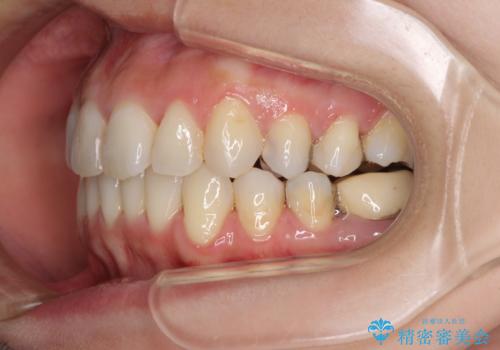

- 上下のデコボコと奥歯の咬みにくさを気にして来院された患者様です。

上顎骨の幅が下顎骨よりも小さいので、拡大装置により骨幅を広げて上下関係を改善し、その後インビザラインにて歯並びを整えることとしました。

上下の骨幅を改善したことで、スムーズに歯列矯正を行うことができました。

矯正治療中に近医で銀歯を外す治療を開始したため、治療後に奥歯の咬み合わせが不十分ですが(こちらは近医での治療により改善するとのこと)、歯列と咬み合わせが改善され、患者様には大変満足していただきました。